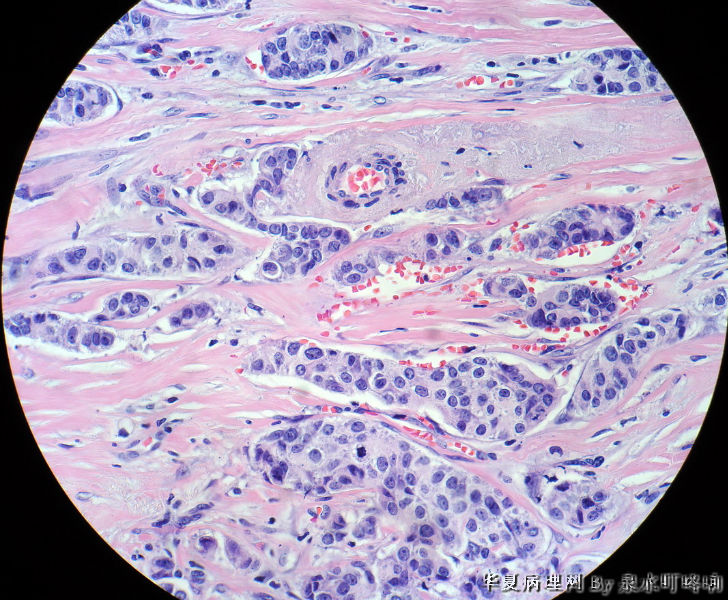

• 右腋下包块图2

图2

皮肤转移癌 脉管内见栓 考虑来自乳腺

最后诊断:浸润性导管癌(分化较低),考虑来自乳腺尾叶或副乳恶变。

女,60岁,右腋下肿物两年余。

大体:灰白带皮组织一块,大小约3.8×2.2×1.4厘米,皮肤呈橘皮样改变,切面灰白,质韧。